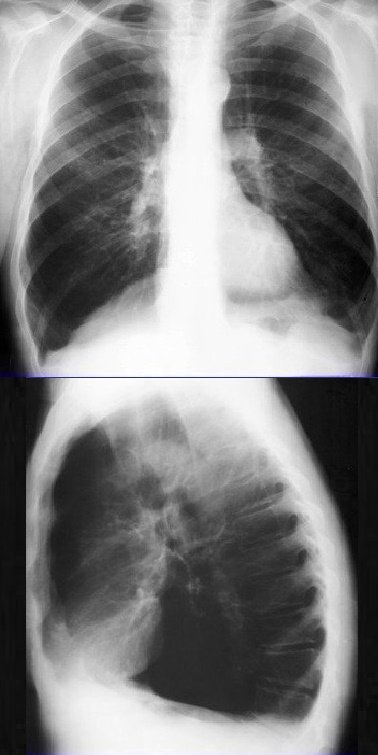

Изучение дозы излучения при рентгеновских исследованиях: визуализация